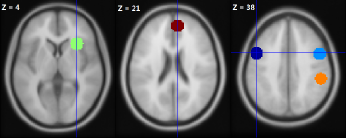

Although the time points when the different types of images were applied to each subject are known, we treated the data as if such information were not available in advance. We applied the proposed change-point detection method to 16 ROIs with the nominal significance level and the dependence estimated by the elbow method. If an ROI was tested to encounter one or more change points, it was activated. Moreover, the type of image induced the change is known at each identified change point. Figure 5 illustrates the physical locations of the ROIs activated (changes detected) by the thin-body images and fat-body images for the normal weight subject and the overweight subject. More precisely, 5 ROIs were activated for the overweight subject when viewing fat-body images, while only 3 ROIs were activated when viewing thin-body images. On the other hand, for the normal weight subject, 8 ROIs were activated when viewing thin-body images, while only 3 ROIs were activated when viewing fat-body images.